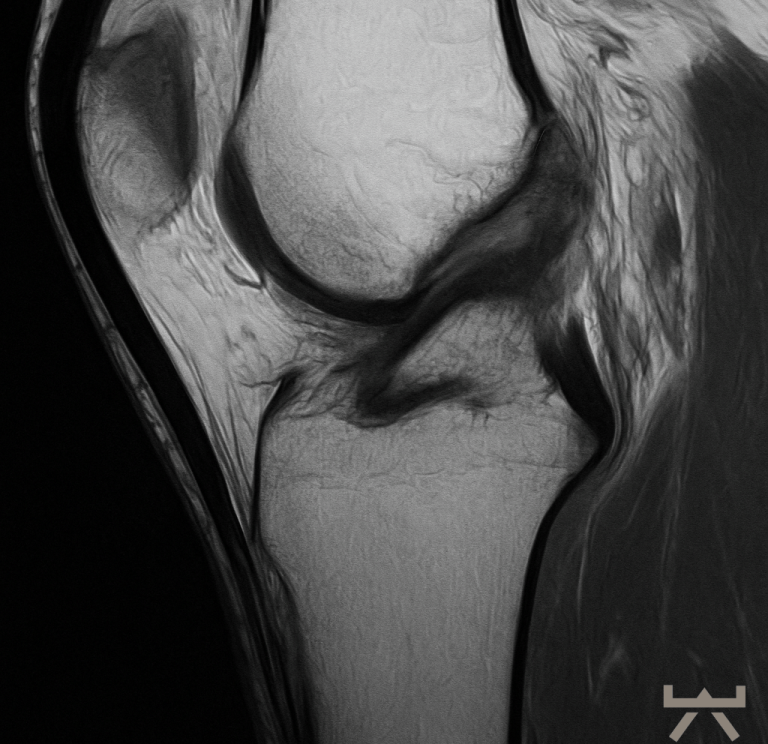

Starke Schmerzen und dadurch eine hohe Muskelspannung können die Durchführung und somit auch die Beurteilung der Tests erschweren. Daher können bildgebende diagnostische Mittel hier eine Alternative sein:

- MRT

- CT

Durch die Schwellung ist die Diagnostik in der Bildgebung jedoch erschwert, daher muss diese nach dem Trauma schnellstmöglich erfolgen oder es kann eine wiederholte Untersuchung in der subakuten Phase sinnvoll sein. Hierfür eignen sich die oben aufgelisteten bildgebenden diagnostischen Mittel, wobei das MRT hier die erste Wahl ist. In diesen Untersuchungen werden die nötigen Strukturen des Knies dargestellt. Auch häufige Begleitverletzungen wie Meniskusschäden oder Verletzungen des Außenbandes können in der Magnetresonanztomographie direkt ausgeschlossen/diagnostiziert werden.